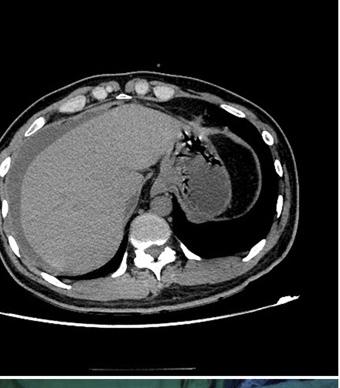

PATIENT HANDOUT: FOCAL LIVER LESIONS

Information for patients to understand growths found on the liver during imaging